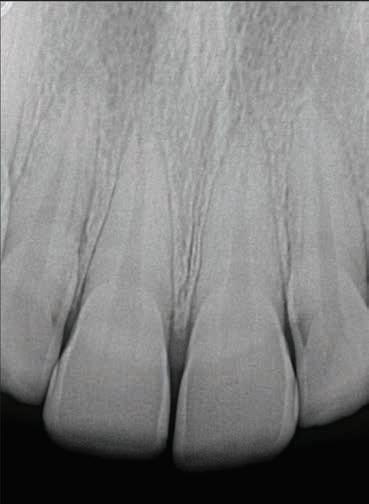

The patient continued to return to his pediatric dentist for routine dental check-ups and preventive visits. Figure 6 shows the clinical and radiographic appearance at 5 years after the traumatic intrusion. Root maturogenesis and apical closure of the maxillary left permanent central incisor is notable. The patient received orthodontic treatment when he was 14 years old, which was 7 years after sustaining dental trauma. Orthodontic treatment spanned one-and-a-half years, during the course of which the pediatric dentist monitored the

maxillary left permanent central incisor for any root and/or pulpal pathosis. Figure 7 shows the radiographic presentation of the tooth during and after orthodontic treatment.

Figure 6. Clinical and radiographic appearance at 5 years after intrusion injury.

Figure 7. Radiographic presentation of the tooth during and after orthodontic treatment (7-8

pulpal and periodontal pathoses for 15 years since the initial trauma. Figure 8 shows the radiograph at 15 years after the traumatic injury.

Figure 8. Radiograph at 15 years after intrusion injury.